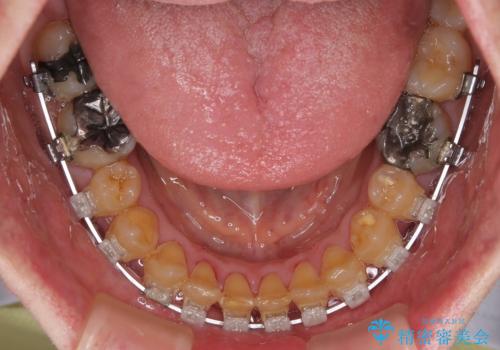

- 矯正装置

- クリアブラケット

- 前歯のデコボコと隙間の空いた歯列を気にして来院された患者様です。

下顎前歯が隠れるほどのディープバイトにより、強い咬合力と突き上げで上顎歯列に隙間が空いている状態でした。

手前に傾斜している奥歯をワイヤー装置で立ち上がらせ、咬み合わせの高さを挙上することで突き上げを解消し、空隙歯列を改善していくこととしました。